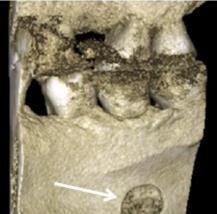

Pacjent nr 1 (mężczyzna, 49 lat): jednokomorowy typ tylny, po lewej stronie żuchwy (Rycina 1). Wymiary SBC wynosiły: mezjo-dystalny 9,3 mm, policzkowo - językowy 4,8 mm i czaszkowo - ogonowy 10,6 mm.

Całkowita objętość wynosiła 473,18 mm3.